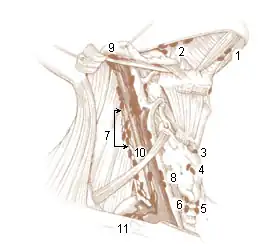

Additional images

-

Lymphatics of pharynx.

Lymphatics of pharynx. -

The lymphatics of the face.

The lymphatics of the face.